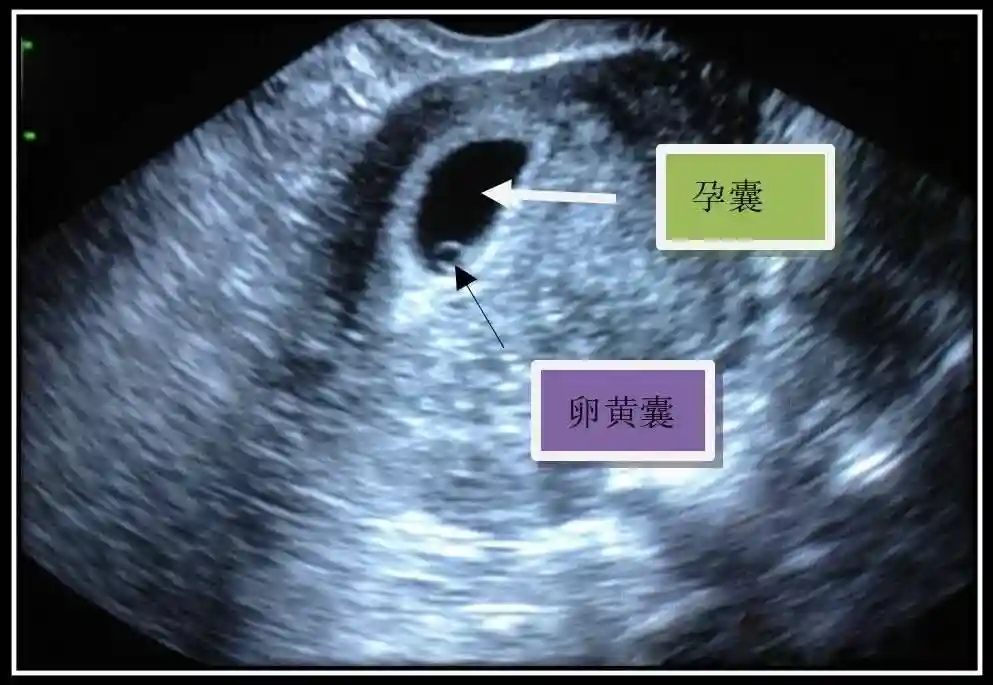

2??卵黃囊:是妊娠囊內(nèi)第一個(gè)解剖結(jié)構(gòu),直徑<7mm。表現(xiàn)為小環(huán)狀,中央為無(wú)回聲,囊壁薄,內(nèi)透聲好。卵黃囊位于胚胎旁胚外體腔內(nèi)。卵黃囊通常在孕5-6周時(shí)出現(xiàn),5-10周穩(wěn)步增長(zhǎng),一般不超過(guò)7mm,至12周消失。妊娠囊的大小與卵黃囊之間有一定關(guān)系,妊娠囊平均直徑> 8 mm 時(shí),經(jīng)陰道超聲均應(yīng)顯示卵黃囊,妊娠囊平均直徑> 18 mm 時(shí),經(jīng)腹超聲均應(yīng)顯示卵黃囊。